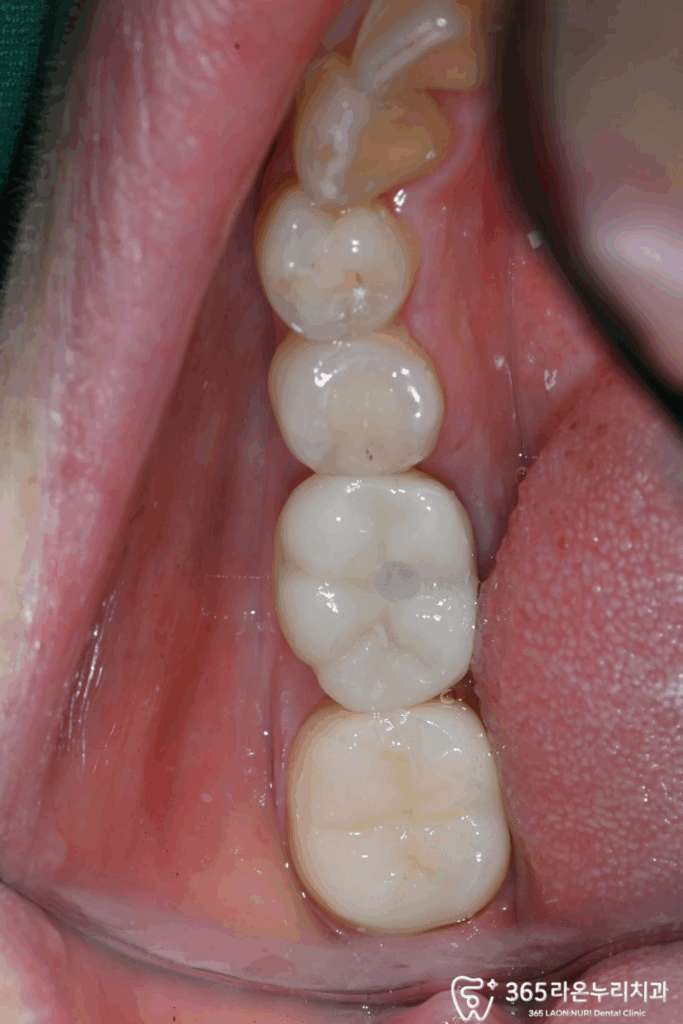

모두 완료된 모습을 보면

충치가 있던 곳도

없어진 것을 볼 수 있는데요.